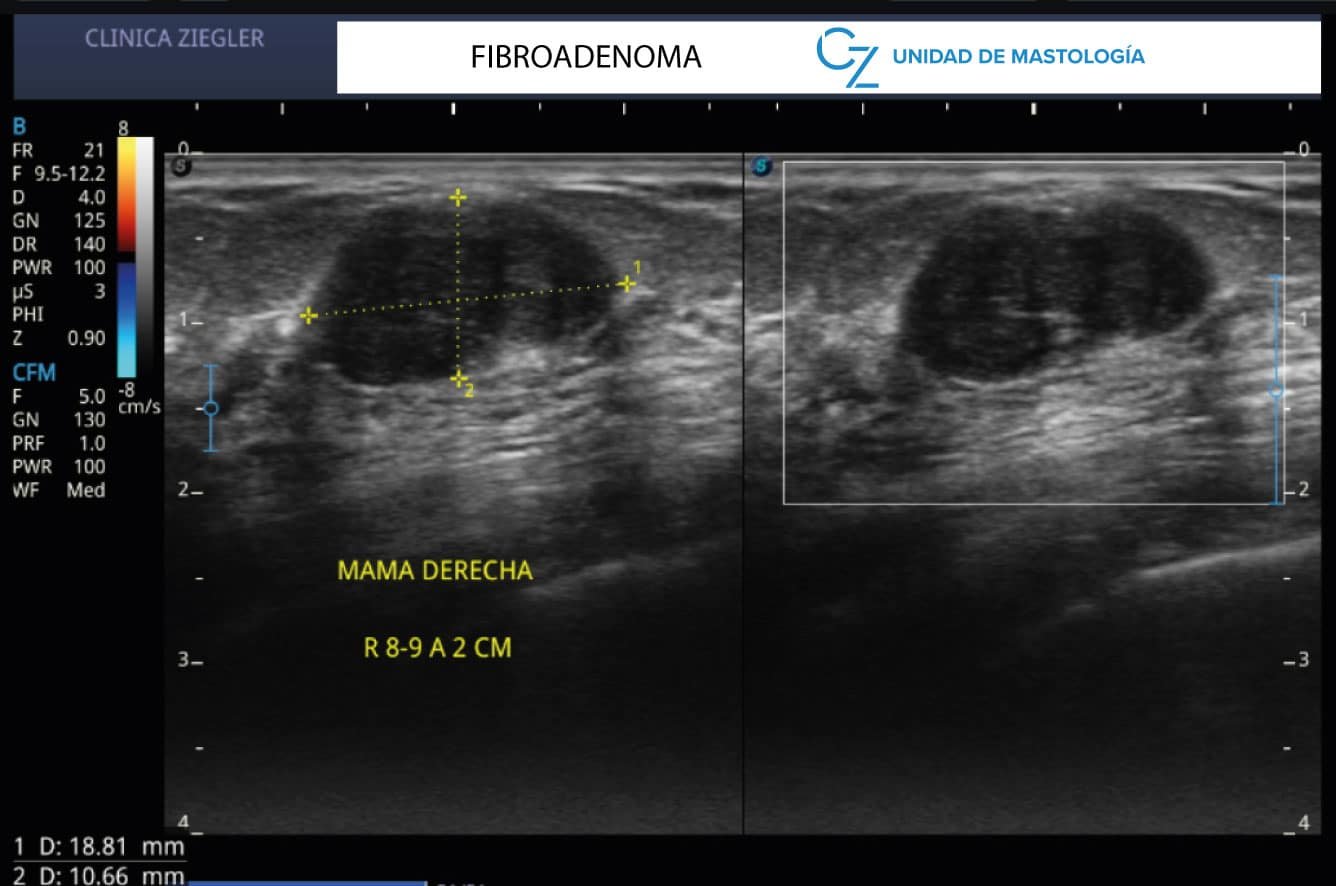

Otras enfermedades de la mama